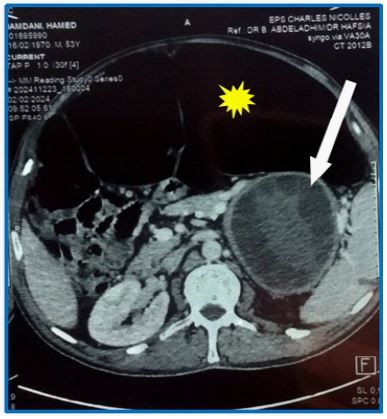

We report the case of a 54-year-old man with a history of sigmoidectomy for volvulus who developed chronic colonic dilatation requiring repeated colonic exsufflation. Abdominal CT imaging revealed pancolonic distension and a large (11 × 9 × 13 cm) multilocular pancreatic tail cyst causing segmental portal hypertension (Figure 1). Hydatid serology was positive, suggesting a diagnosis of a pancreatic hydatid cyst. The patient underwent an exploratory laparotomy. Intraoperatively, the entire colon was distended (Figure 2A), and a well-defined cys t ic lesion was found in the pancreatic tail, which was densely adherent to the spleen and associated with collateral venous circulation (Figure 3A). We performed a subtotal colectomy (Figure 2B) without immediate restoration of intestinal continu ity, combined with partial resection of the pancreatic hydatid cyst (Figure 3B). The cyst contents, consisting of non-infected multivesicular fluid (Figure 3C), were completely evacuated. A drain was placed in the residual cavity. Postoperative recovery was uncomplicated, with no recurrence at 6-month follow-up.

Figure 1: Axial contrast-enhanced abdominal CT showing colonic distension (*) and a multilocular pancreatic cyst (white arrow)